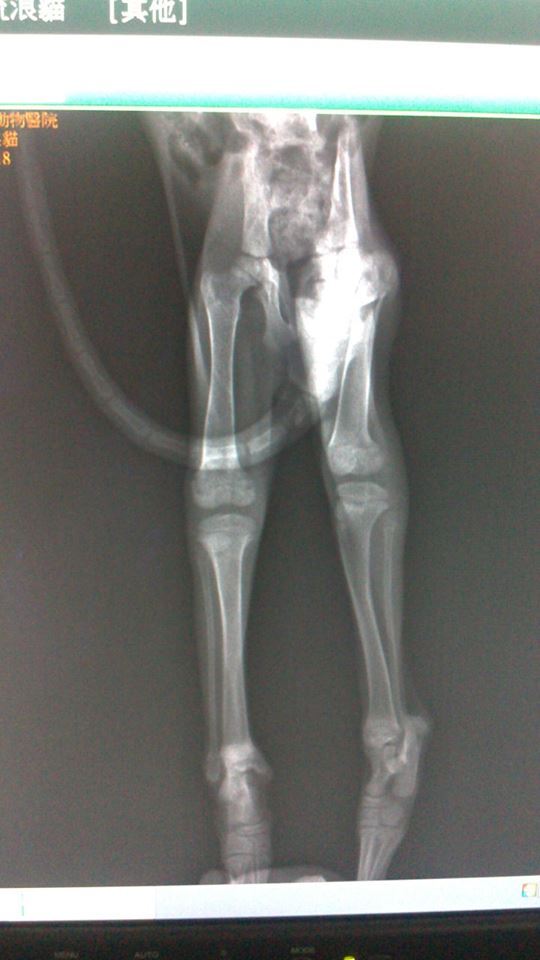

主題: 小灰灰 大腿骨折 申請者姓名: 程修玲 花色: 申請日期: 2013-11-05 07:36:20 申請者部落格: 申請者臉書網址: 所在縣市/合作醫院: 新北市/新北動物醫院 治療費用: 5000元 需求人數: 6人 已結案 (2014-01-10 17:54:23) 報名人員: 錢快來(已付款)、李采庭(已付款)、Tiffany Chang(已付款)、Bear(已付款)、柯元傑(已付款)、Janett Wang(已付款)、 候補人員: Hui Chung Shee、 動物病情說明: 說真的 這隻小灰灰會出現在汐止水蓮社區 讓愛媽很洩氣 因為社區愛媽 先前花了 快三年的時間 將社區裡頭近一百隻的浪浪都結紮了 現在竟然出現小灰灰 而且才兩個月 因為最近社區已結紮的浪貓 常為了地盤而叫囂 小灰灰可能為了躲避從近三層樓高的花台墜落而摔斷腿 一樓住戶原本要通報收容所 被我們攔截下來 花了一天一夜的時間誘捕 終於讓小灰灰入籠 經x光看到他的右大腿骨已經摔到錯位了 雖然他還小 其實開刀打麻醉有風險 可是不開他一定癱瘓 經討論之後 還是決定讓他開刀 希望能恢復他的大腿功能 動物近況說明: 小灰灰送醫後兩天後開刀 但術後恢復狀況不佳